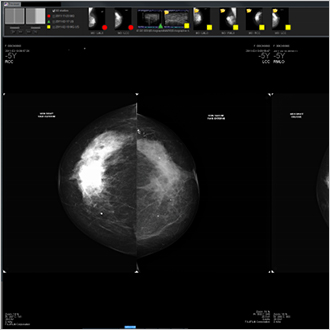

TM-Mammo

The TM-Mammo solution was developed specifically to satisfy the storage, distribution and diagnostic needs of all digital mammographic imaging produced in senology departments. The TM-Mammo viewer allows easy comparison with the patient's multi-image history (all modalities) and viewing of user-specific display sequences. Tomosynthesis is an integral part of display reports.